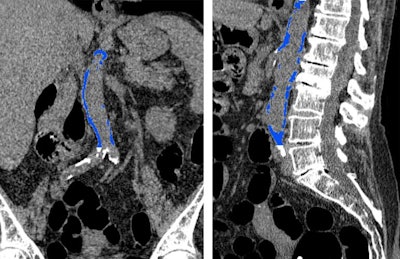

CT colonography scan showing abdominal aortic calcification (blue). Image courtesy of RSNA.

CT colonography scan showing abdominal aortic calcification (blue). Image courtesy of RSNA.Predicting cardiovascular events